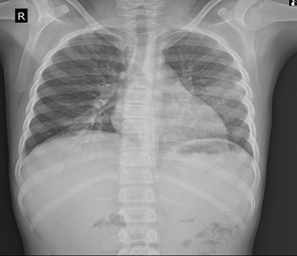

Chest radiograph

revealed an ill-defined opacity in the left mid zone (Figure 1).

Figure 1: Chest radiograph

revealing an ill-defined opacity in the left middle zone (arrow)